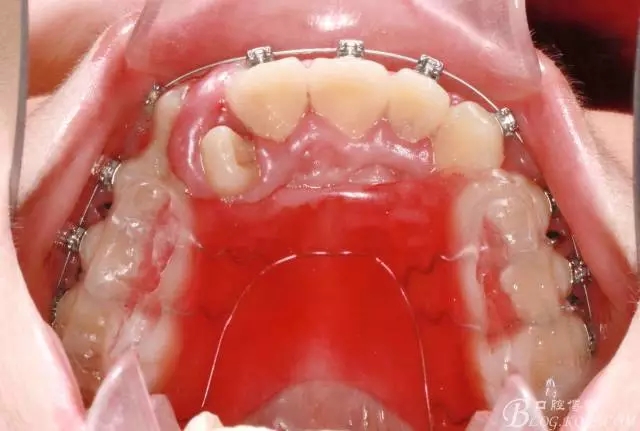

前牙反合伴擁擠的案例

通常情況下,前牙反合的患者因上頜發(fā)育不足,會(huì)伴發(fā)上頜前牙區(qū)牙列擁擠;

患者13歲,男性,自覺(jué)牙齒不齊要求矯正;